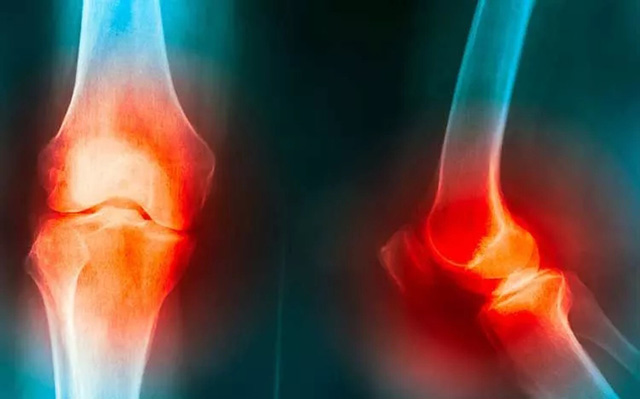

研究表明,60岁以上的人群中,50%以上的人会出现不同部位的骨性关节炎,而膝关节是发病率最高的部位。很多人就认为膝关节炎是老年人的“专利”,其实不然,告诉大家:膝关节衰老从30岁开始,年轻人要重视膝关节的保护。

年龄是导致膝骨关节炎最常见的原因。几乎每个人最终都会发展成某种程度的骨关节炎。但其他还有很多因素,也会增加患膝关节炎的风险。